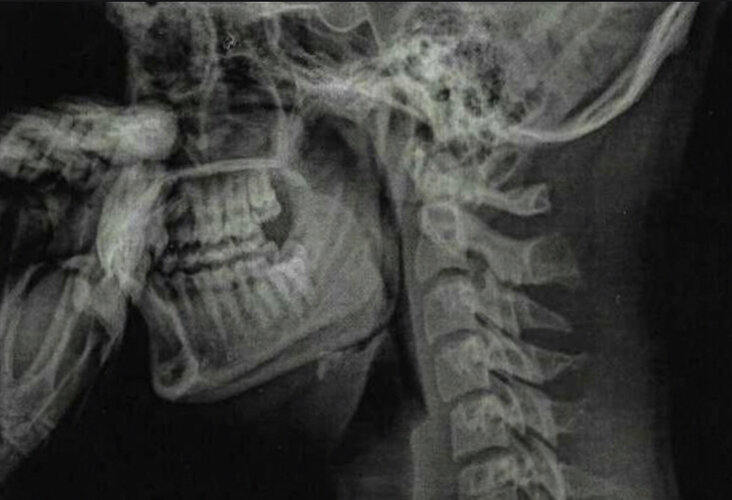

So as I said i’ve been softmaxxing for 2 years now i’m 18 and think It might be over. I think of doing a BSSO to fix my mandibular rotation and slight overbite but that’s gonna take a long time. I need someone the tell if there is anything left so I can start slaying ltbs.